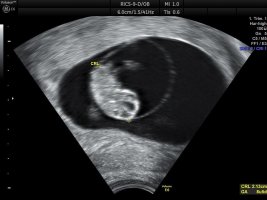

Fikk se verdens minste armer, bein og hode

Hun målte lille til 2,13 cm og nøyaktig 8+5 i dag, som er nøyaktig samme dagen jeg har